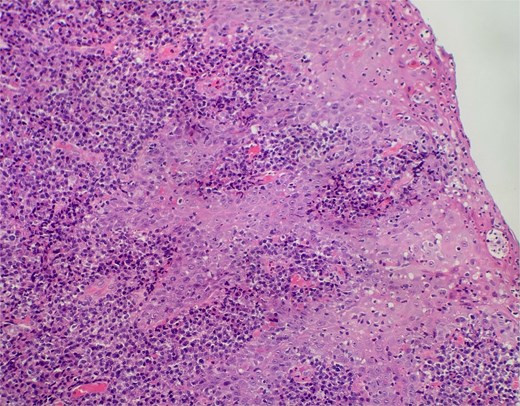

On clinical examination, harsh stridor with increased work of breathing was noted. Flexible nasoendoscopy demonstrated generalized supraglottic oedema with impending upper airway obstruction. Intravenous dexamethasone was commenced. A surgical tracheostomy with laryngeal biopsies under general anaesthetic was carried out. Histological examination (Figs 1 and 2) demonstrated hyperplastic, hyperkeratotic squamous mucosa with reactive atypia and an underlying dense polyclonal plasmocytic inflammatory infiltrate. No granulomata, prominent eosinophils, or stigmata of vasculitis were seen. Connective tissue disease screening demonstrated normal antinuclear antibody levels with positive perinuclear anti-neutrophil cytoplasmic antibodies. Anti-proteinase 3 levels returned as 3.7 IU/ml (range 0–1.9), while antimyeloperoxidase levels were normal. Rheumatology was consulted, and a provisional diagnosis of PCM was made. Serial laryngoscopy demonstrated resolution of the oedema, with the supraglottis regaining a normal appearance despite gradual tapering of the intravenous dexamethasone. A tracheostomy capping trial was successful. The patient was decannulated uneventfully and discharged on oral prednisolone. Three months later, he was maintained on 5 mg prednisolone—attempts to taper any further caused symptoms recurrence. Outpatient referral was made to Rheumatology for medical management with steroid-sparing therapy. Unfortunately, the patient was lost to follow-up due to failure to attend for outpatient review.

Slide from epiglottis specimen at index presentation showing squamous mucosa and underlying polyclonal plasmocytic infiltrate.

Slide from index presentation under higher magnification again demonstrating plasmocytic infiltration.